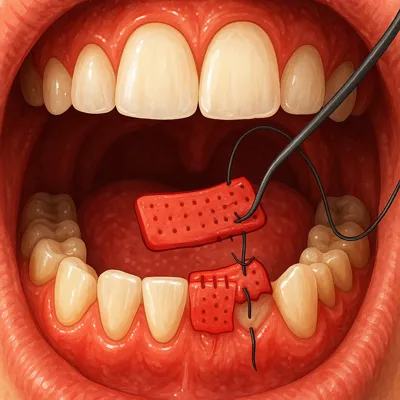

انجام برش یا پیوند: بسته به روش انتخابی (مانند جراحی فلپ، پیوند لثه یا جینجیواکتومی) لثه برش داده میشود یا بافت جدید پیوند زده میشود تا ناحیه آسیبدیده ترمیم گردد.

بخیه و پانسمان: پس از اتمام عمل، بافت لثه بخیه زده شده و در صورت نیاز پانسمان مخصوص قرار داده میشود تا روند بهبودی تسریع شود.

بافت ملتهب دهان و لثه در حال جراحی بافت نرم و درمان عفونت دندان